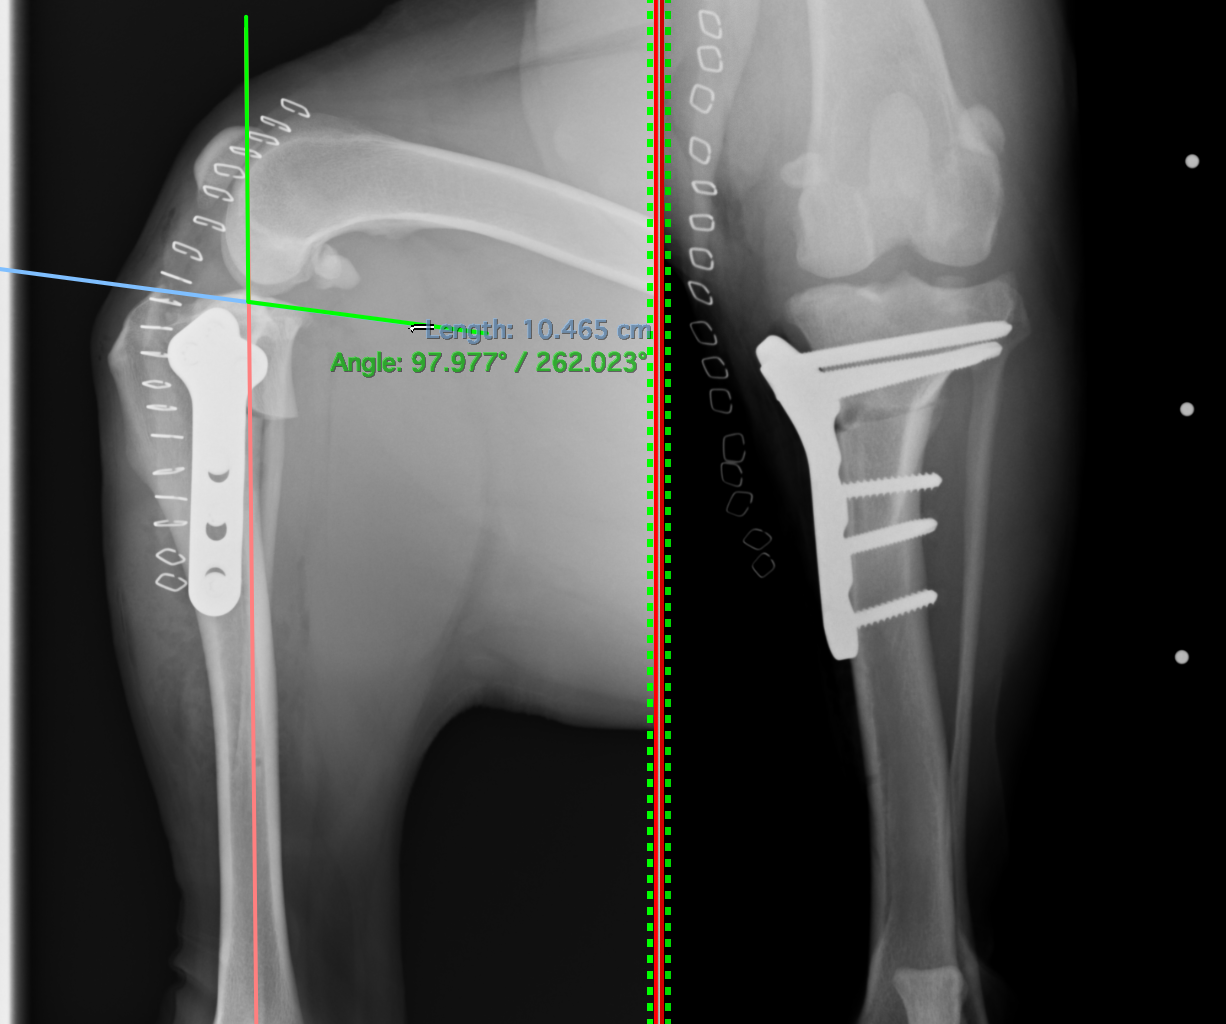

脛骨高平部角(TPA)と呼ばれる角度です。これが高いために前十字靭帯が切れやすくなります。

手術の際にはこのように様々な角度や距離を測定し、円の部分で骨切りを行います。

術後のレントゲン画像です。先程までずれていた矢印が合っているのがわかります。

またTPAと呼ばれる角度も小さくなっているのが確認できます(6°)。6°前後が理想的と言われています。